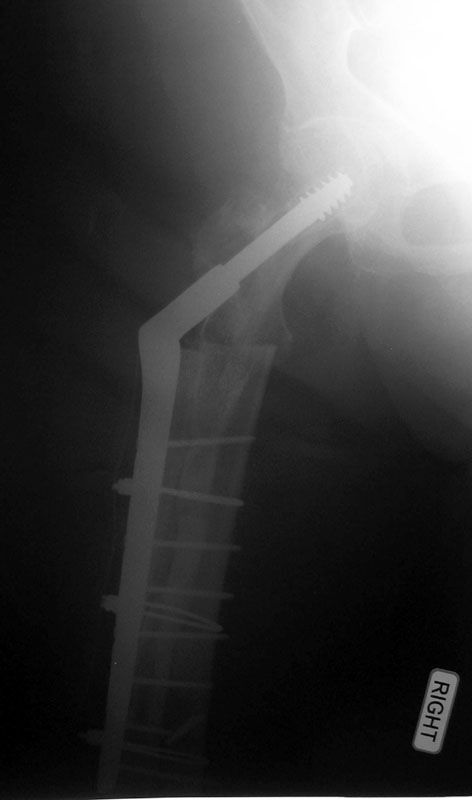

08/26/02 AP

08/26/02 lat

01/17/03 AP

01/17/03 lat